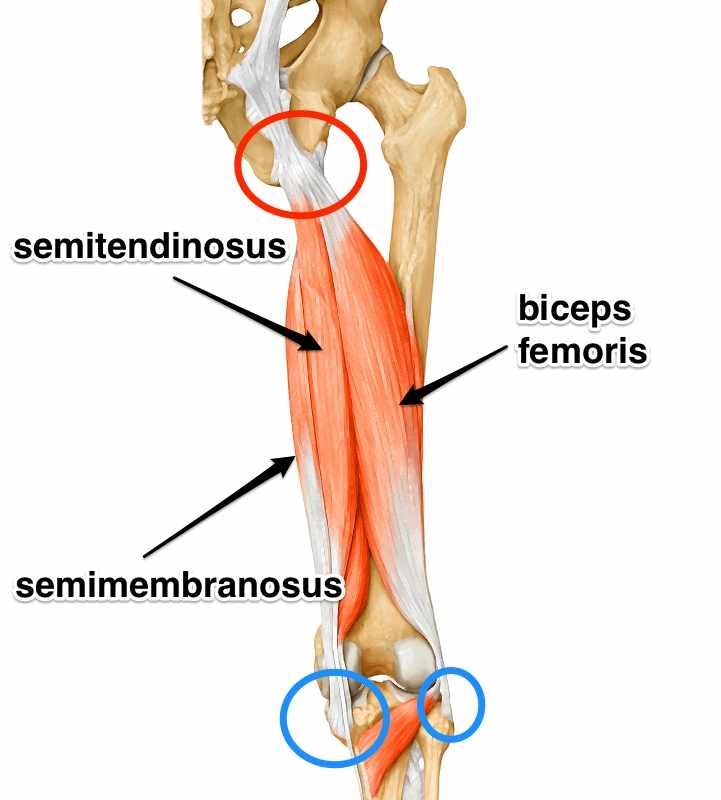

Анатомия и Функции Мышцы Adductor Magnus